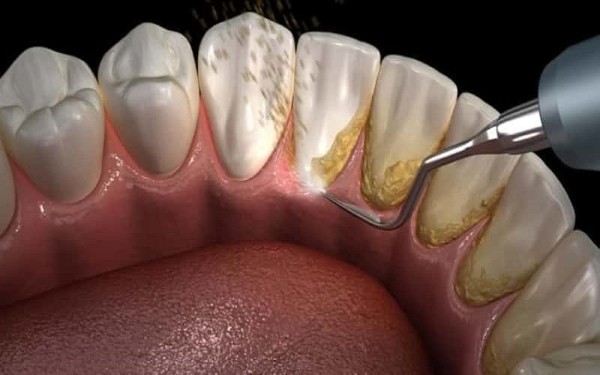

Vai trò của việc lấy cao răng định kỳ

Việc lấy cao răng định kỳ là cách hiệu quả để làm sạch và giữ cho răng miệng khoẻ mạnh. Các lợi ích bao gồm:

- Giảm nguy cơ viêm nướu, sâu răng và các bệnh lý nghiêm trọng.

Lấy cao răng định kỳ là một cách hiệu quả để ngăn ngừa chuỗi rối loạn khác như sâu răng hay viêm nha chu. Thông qua quá trình này, bạn có thể loại bỏ vi khuẩn và các mảng bám gây hại.